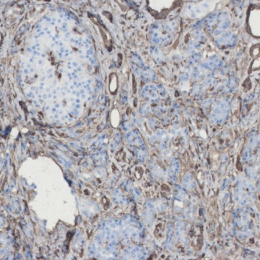

H&E | ANXA1 | ANXA10 | ANXA13 | |

|---|---|---|---|---|

Cancer tissue | ![]() | ![]() | ![]() | ![]() |

Cancer organoid | ![]() | ![]() | ![]() | ![]() |

Unlock the essence of precision in cancer treatment with our PC organoids, mirroring the genetic markers of pancreatic cancer.